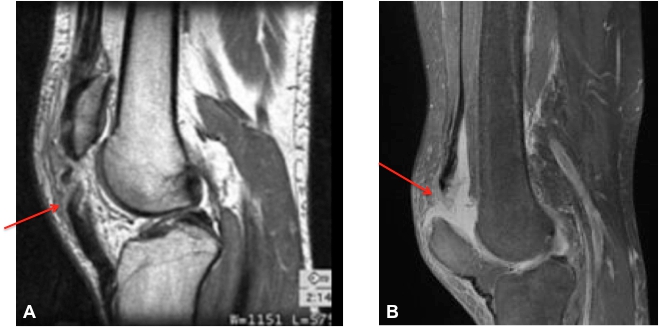

Figure 1. IRM du genou. A. Rupture du tendon rotulien. B. Rupture du tendon quadricipital.

Le diagnostic est essentiellement clinique mais il peut être retardé car les symptômes présentés peuvent mimer ceux d'une entorse du genou. En cas de doute, des examens complémentaires (Radiographies, échographie ou IRM) peuvent être demandés pour confirmer le diagnostic.

Elles surviennent le plus souvent lors d’un traumatisme, une contraction brutale du quadriceps ou lors d’un choc direct.

Le tendon peut alors se rompre à différents endroits : en plein corps du tendon ou sur l’insertion du tendon sur la rotule, créant parfois une petite fracture.

Le diagnostic est essentiellement clinique. Lorsque la symptomatologie n’est pas très claire, des examens complémentaires (radiographies, échographies ou IRM) peuvent être demandés.